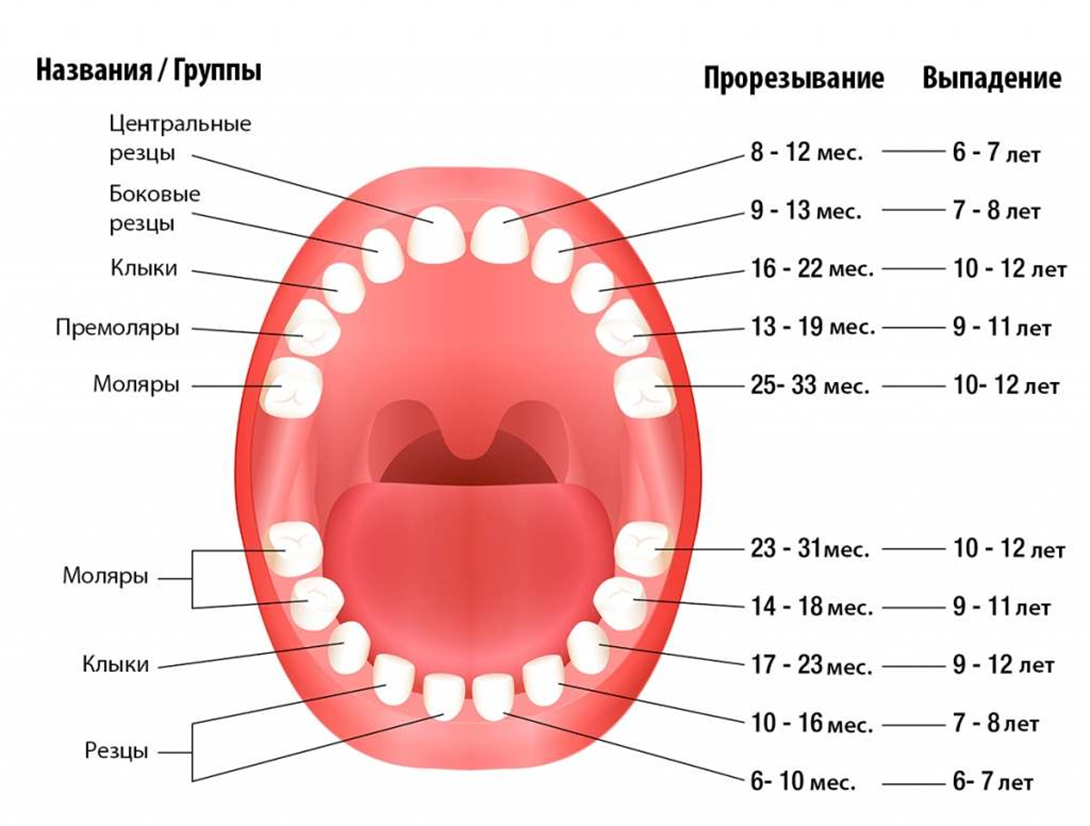

В каком возрасте выпадают молочные зубы у детей?

Во сколько лет выпадают молочные зубы у детей? Смена молочных на коренные начинается в среднем с 5-6 лет, но процесс, предшествующий выпадению происходит еще задолго до этого. Начиная с 4-6 лет, у ребенка рядом с молочными зубами прорезываются третьи моляры (самые дальние в зубном ряде, так называемые «шестерки»), которые являются первыми постоянными зубками.

Выпадают они в течение 5-8 лет, начиная с 5-летнего возраста и до достижения ребенком 13 лет. К 14 годам зубной ряд подростка должен состоять из всех коренных зубов.

При этом процесс, сроки и порядок выпадения будет зависеть от того, в какой последовательности и когда прорезались зубки у младенца. Чем позже появились первые зубы, тем дольше не будет происходить их смена на постоянные. Прорезываются коренные зубы симметрично с двух сторон. У девочек этот процесс начинается раньше, у мальчиков – немного позже.

В большинстве случаев зубы, находящиеся снизу, выпадают раньше, чем соответствующие им резцы, клыки или моляры, находящиеся в верхней челюсти.

Когда выпадают молочные зубы у детей

Процесс смены достаточно длительный. Знание сроков помогает родителям определить причину появления болей и отека десны. Начинается этот период примерно к 6-7 годам. Продолжается смена 6-7 лет и завершается к 12 годам. Сколько именно займет период, зависит от индивидуальных особенностей ребенка и его здоровья. Примечательно, что у девочек временные зубы выпадают быстрее, чем у мальчиков.

Молочные зубы у детей: схема выпадения

Выпадение начинается с резцов и далее в том же порядке, что и их прорезывание. В норме выпадать зубки у ребенка должны согласно следующему графику:

- Центральные резцы выпадают к 6-7 годам.

- Вторые резцы начинают выпадать к 7-8 годам.

- Первые моляры выпадают к 10 годам.

- Клыки и вторые моляры к 12 годам также заменяются на постоянные.

Стоит помнить, что возраст указан условно. Если сказано, что начинается выпадение в 6 лет, то смена может происходить в пять лет или в семь. Кроме того, коренные зубы у ребенка растут на свободном месте, поэтому появляются раньше, чем начинают выпадать молочные. Впервые прорезываются они иногда уже к пяти годам, но при этом они являются постоянными.